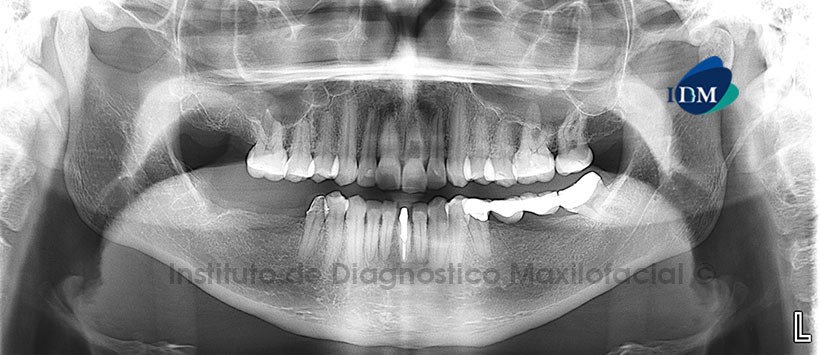

Paciente femenino, 37 años de edad, es referido al Instituto de Diagnóstico Maxilofacial (IDM) para evaluación general.

A la evaluación de la radiografía panorámica se aprecia neumatización de senos maxilares con engrosamiento de la mucosa sinusal a predominio del lado derecho, se aprecia además múltiples restauraciones y tratamientos protésicos a nivel de las piezas 3.7, 3.5 y 4.5. Se nota además una imagen radiolúcida proyectada a nivel del tercio cervical y medio de la pieza 2.1, imagen sugerente de probable reabsorción radicular interna, se decide realizar una tomografía volumétrica considerando el tamaño importante de la aparente alteración. (Figura 1).

A la evaluación de la tomografía volumétrica (CBCT) en cortes axiales (Figura 2), transaxiales (Figura 3) y tangenciales (Figura 4), se evidencia reabsorción radicular interna a nivel del tercio radicular cervical y medio, sin alterar el tercio apical produciendo el adelgazamiento de las paredes dentinarias a esos niveles sin comprometer el espacio del ligamento periodontal. Se nota también la disminución de la longitud radicular de la pieza 2.1 con respecto a su contralateral.

En las reconstrucciones 3D se observa claramente la reabsorción radicular interna (Figura 6)

Conclusión: Reabsorción radicular interna severa de la pieza 2.1